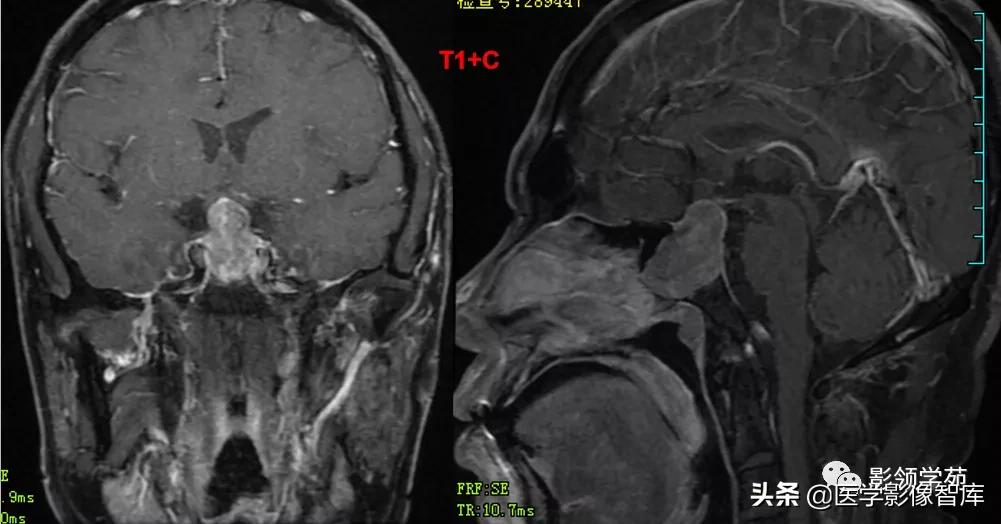

女 61岁 反复头晕3年余

鞍上可见一类圆形均匀稍高密度灶,CT值约47HU,

边界清楚,其内见一小点片状钙化灶;继发鞍上池受压伴变性。

鞍区占位肿块,呈等T1等T2信号,信号均匀,边界清楚。

病灶呈均匀、显著强化(馒头样),以宽基底与前颅窝底相连,

冠状位和矢状位见脑(硬)膜尾征;

肿块突入鞍上池,向上推压视交叉,后缘紧邻垂体柄,与双侧颈内动脉相邻。

(脑膜尾征:增强扫描,肿块邻近的增厚硬脑膜呈窄带状强化,随着远离肿瘤

而逐渐变细。)

颅内动脉走形自然,管壁光滑,未见局灶性异常狭窄或扩大征象。

男 62岁,右眼视朦半年

鞍区见一类圆形稍高密度肿块影,密度较均匀,边界较清,位置稍偏右,向上突入鞍上池内,周围骨质未见破坏。

前颅窝底、鞍前区见一肿块影,呈等T1等T2信号,信号均匀,边缘清楚,以宽基底与颅底接触。

病灶呈均匀明显强化(馒头样),见脑膜尾征;肿块后缘部分进入鞍内,挤压垂体前方和视交叉,垂体柄显示不清楚。

右侧大脑前动脉A1段完全被肿瘤包绕;左侧大脑前动脉A1段与肿瘤分界不清,但无明显包绕和推移。双侧海绵窦未见异常征象。